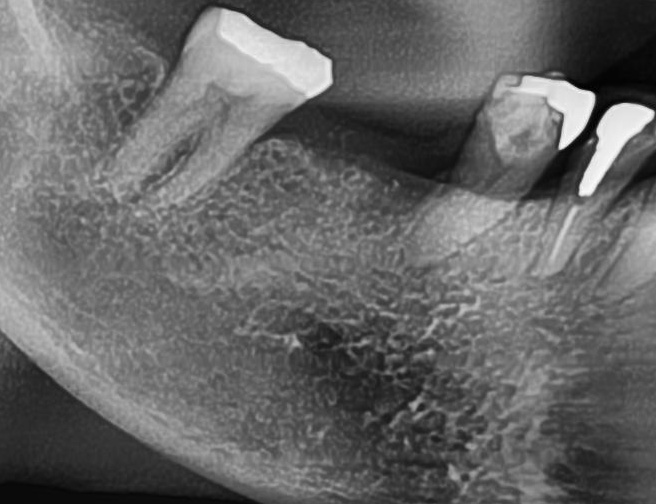

しっかりとインプラント埋め込まれた後は、動揺がないか、噛んだ時に当たらないかなどを確認して、最後にパノラマ写真を撮影して今回のオペは終了となりました。

その後は定期的にお掃除や検診に通院していただき、約3か月経過した後に、きれいな差し歯を入れていきます。